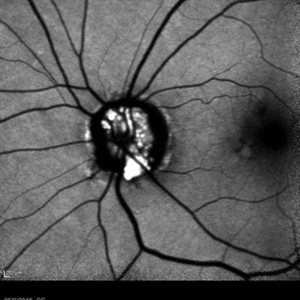

Syphilis Neuroretinopathy

Female patient, 21-years-old, with complaint of low vision in the right eye for 3 years. According to information from the patient's history, at the time she noticed the low vision, it also coincided with a picture of a strong urinary infection as well as episodes of constant tonsillitis. Yes, the patient did not seek medical attention and self-medicated with antibiotics. In ophthalmologic evaluation, as well as examinations of color retinography and ocular fundus autofluorescence, important pigmentary alterations were observed following vascular arches with pigment mobilization in osteoclasts (aspect of a unilateral pigmentary retinitis secondary to the inflammatory process). Which suggested inflammatory process sequelae. Through the laboratory tests, he had positive (+) confirmation for SYPHILIS NEURORETINOPATHY .

Photographer: JEFFERSON R SOUSA - Study Center and Ophthalmological Research Dr. Andre M V Gomes, Institute Dr. Suel Abujamra São Paulo-Brazil

Imaging device: Fundus camera Topcon TRC-50 DX, Imaginet 5.0, angle de 50 graus. Flash 100 / Mosaic with 10 images.

Condition/keywords: autofluorescence imaging, neurosyphilitic optic atrophy, retinitis pigmentosa, syphilis, syphilis neuroretinopathy